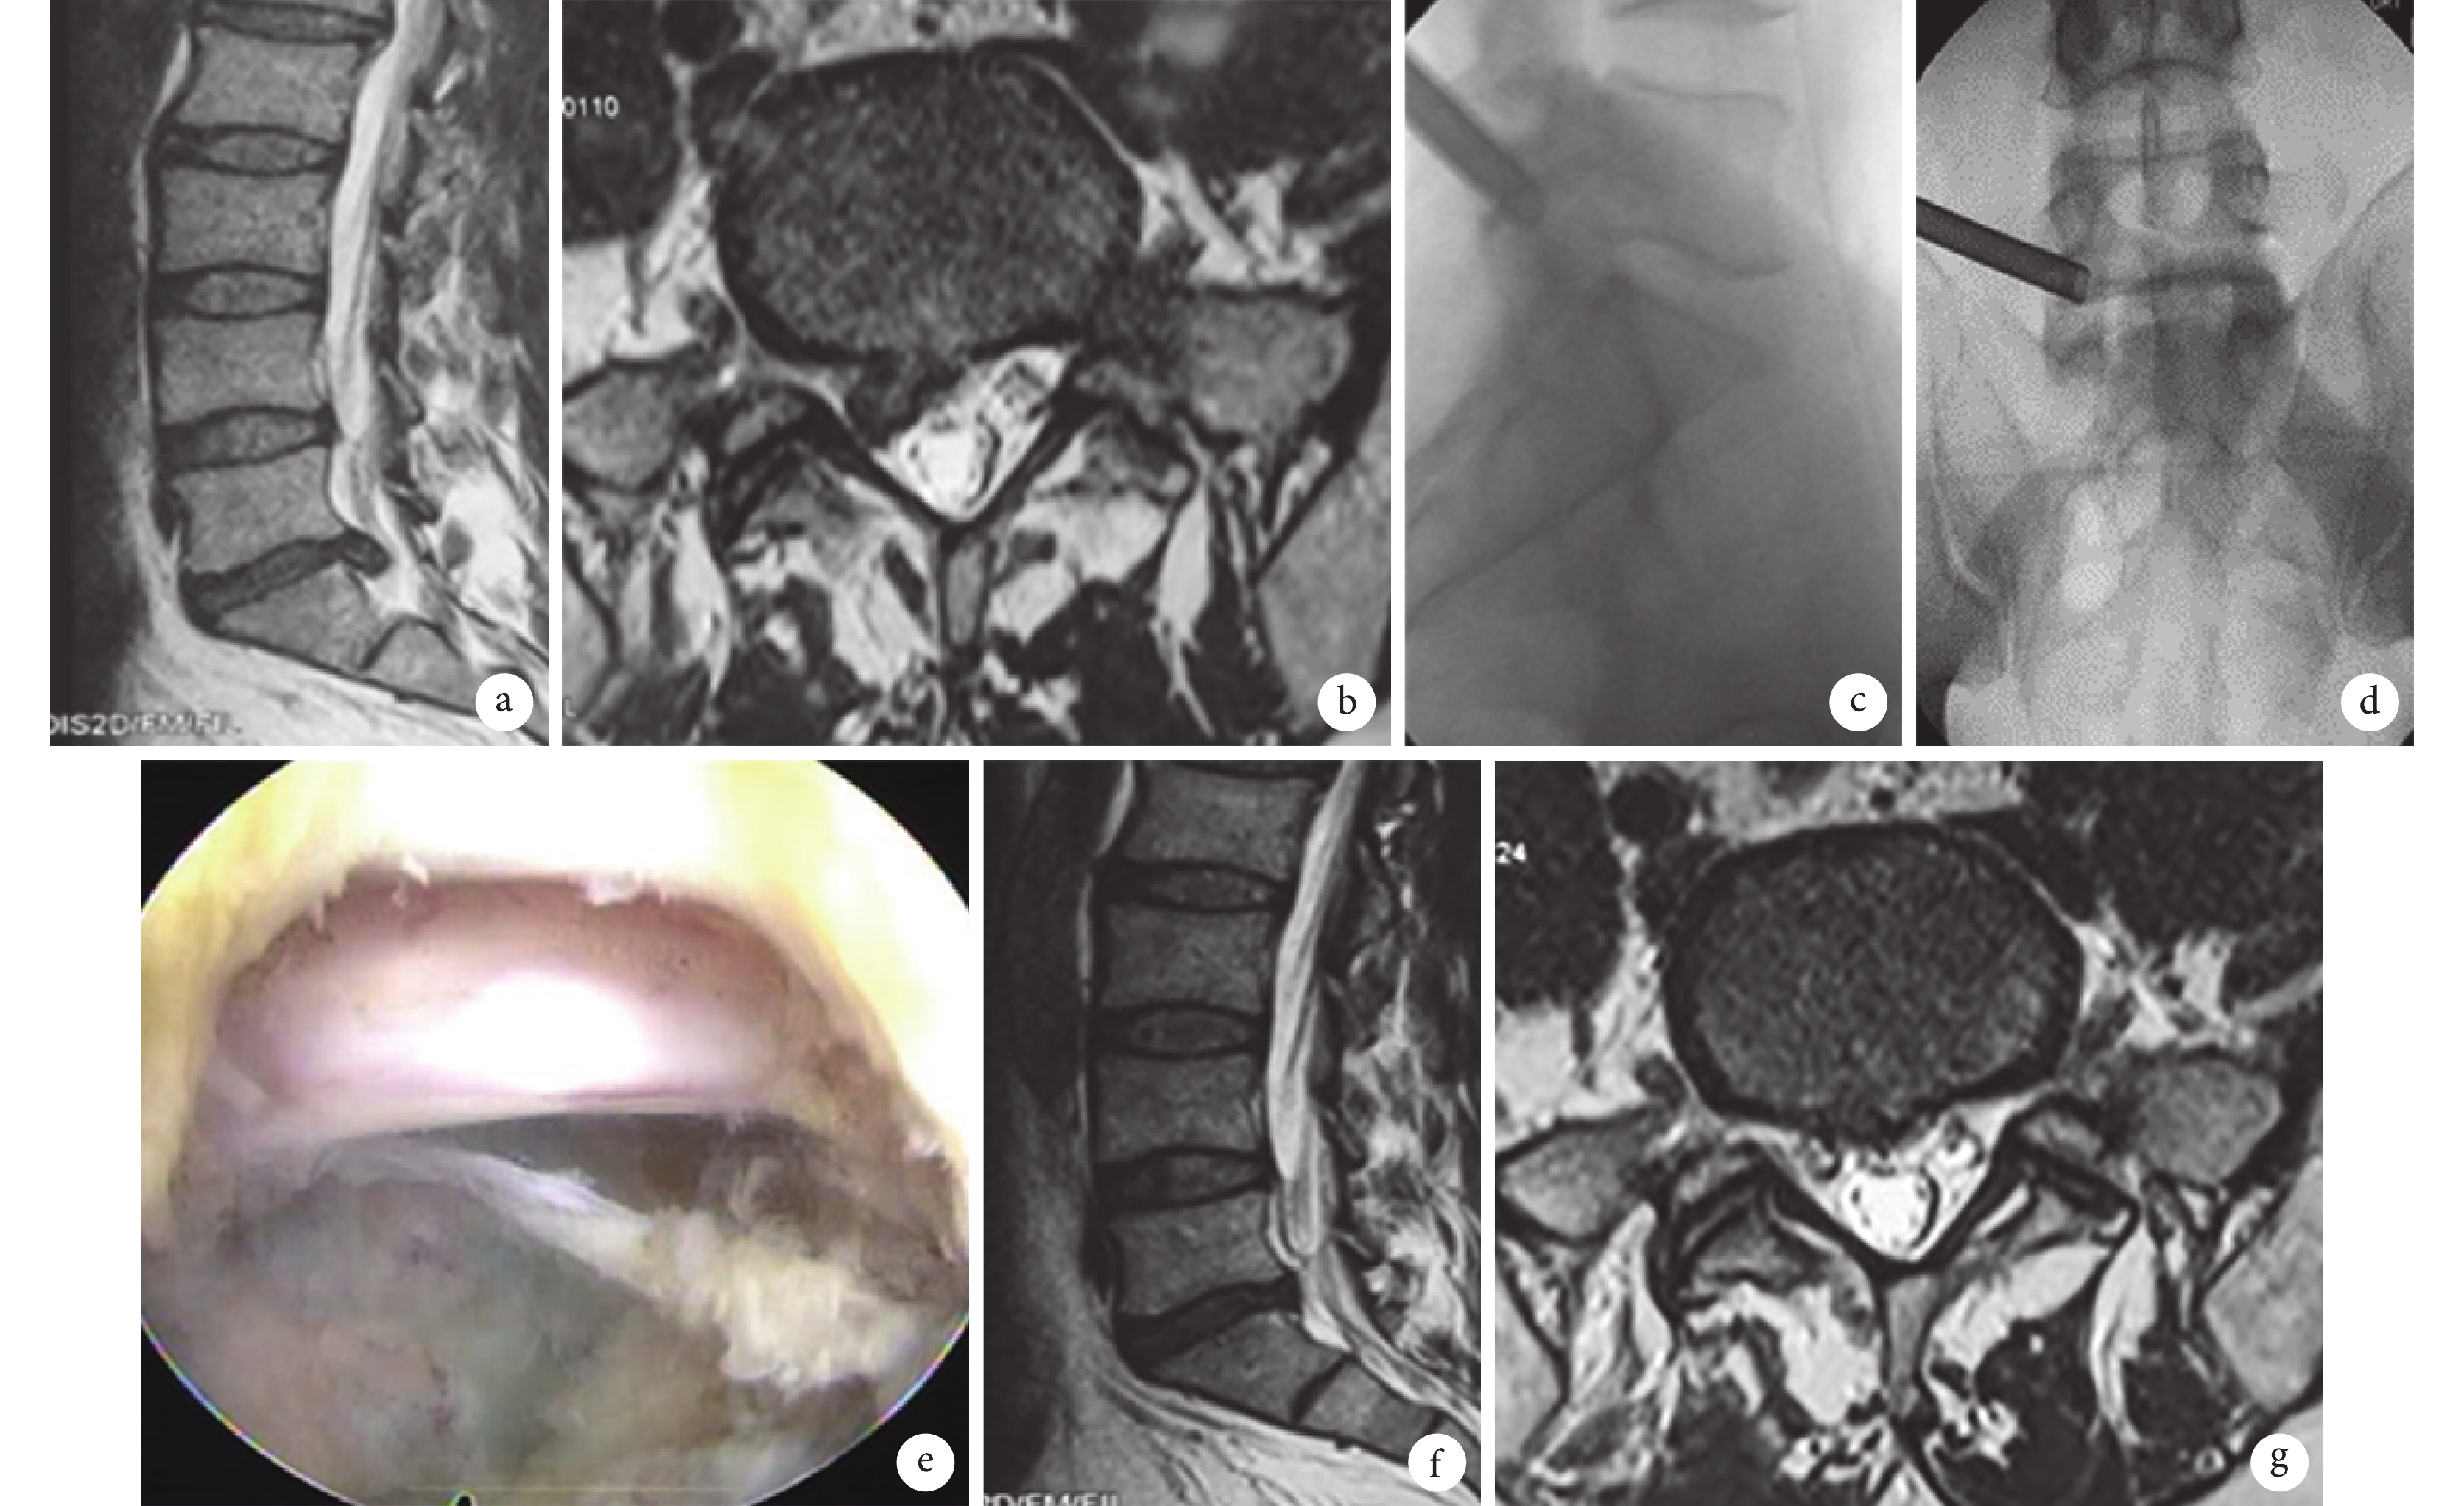

患者,男,47 歲,L5、S1 椎間盤突出癥致右臀部疼痛

a、b. 術前腰椎 MRI 示 L5、S1 椎間盤向右側突出,壓迫硬膜囊及神經根;c、d. 術中操作套管位置良好;e. 內鏡下神經根減壓情況;f、g. 術后 3 個月腰椎 MRI 示突出的髓核基本摘除,硬膜囊和神經根減壓充分

Figure1. A 47-year-old male patient with right buttock pain associated with disc herniation at L5, S1a, b. MRI before operation, showing disc herniation at L5, S1 which compressed the dural sac and right never root; c, d. Fluoroscopic images of proper position of the working cannula; e. Decompression of the nerve root under endoscopy; f, g. MRI at 3 months after operation, showing the herniated nucleus pulposus was removed and the dural sac and nerve root compression were relieved